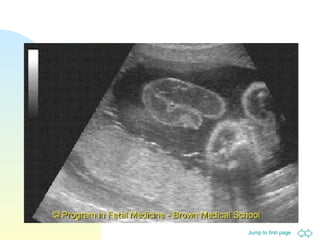

Omphalocele

Defect is covered by a surrounding

membrane (peritoneum and

amnion)

Umbilical cord inserts into the sac

Typically contain bowel and/or

liver, stomach and spleen